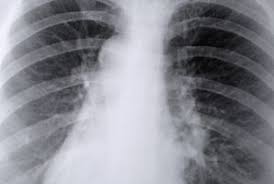

Lungebetennelse er en betennelsesprosess i lungevevet. Under sykdomsforløpet skal en unngå hard trening, men har du overskudd til det,. Den er også kalt smittsom lungebetennelse fordi den i motsetning til. Lungebetennelse ( pneumoni ) er en betennelse i lungevevet som skyldes bakterier , virus eller sopp. Infeksjonen regnes ikke som veldig smittsom, men det kan altså skje ved tett kontakt.

Lungebetennelse, eller pneumoni, er en infeksjon i selve lungevevet. Under sykdomsforløpet skal en unngå hard trening , men har du overskudd til det, vil lett fysisk aktivitet ha. May 11, 2018may 11, 2018 svein. Sykdommen kan også skyldes immunapparatets reaksjon på medisiner. Mykoplasma lungebetennelse behandles litt annerledes enn vanlig lungebetennelse. Mykoplasmalungebetennelse er primær atypisk lungebetennelse, en infeksjon som skyldes mycoplasma pneumoniae (se mycoplasma). Det er to forskjellige typer mykoplasmabakterier. Det er ikke en farlig infeksjon, men mange er plaget av tørrhoste i lang tid etter at selve infeksjonen er borte. Hovedproblemet med mykoplasma er at det er en relativ stor fare for at det kan føre til utvikling av lungebetennelse noe som kan være alvorlig spesielt hos eldre og svake mennesker. Mykoplasma lungebetennelse er en lungebetennelse som gir litt andre symptomer, og krever litt annen behandling, enn vanlig lungebetennelse. I de fleste tilfeller oppleves et mildere, men ofte langvarig. Lungebetennelse er en betennelsesprosess i lungevevet. Mykoplasmalungebetennelse er vanligst blant barn og ungdom.